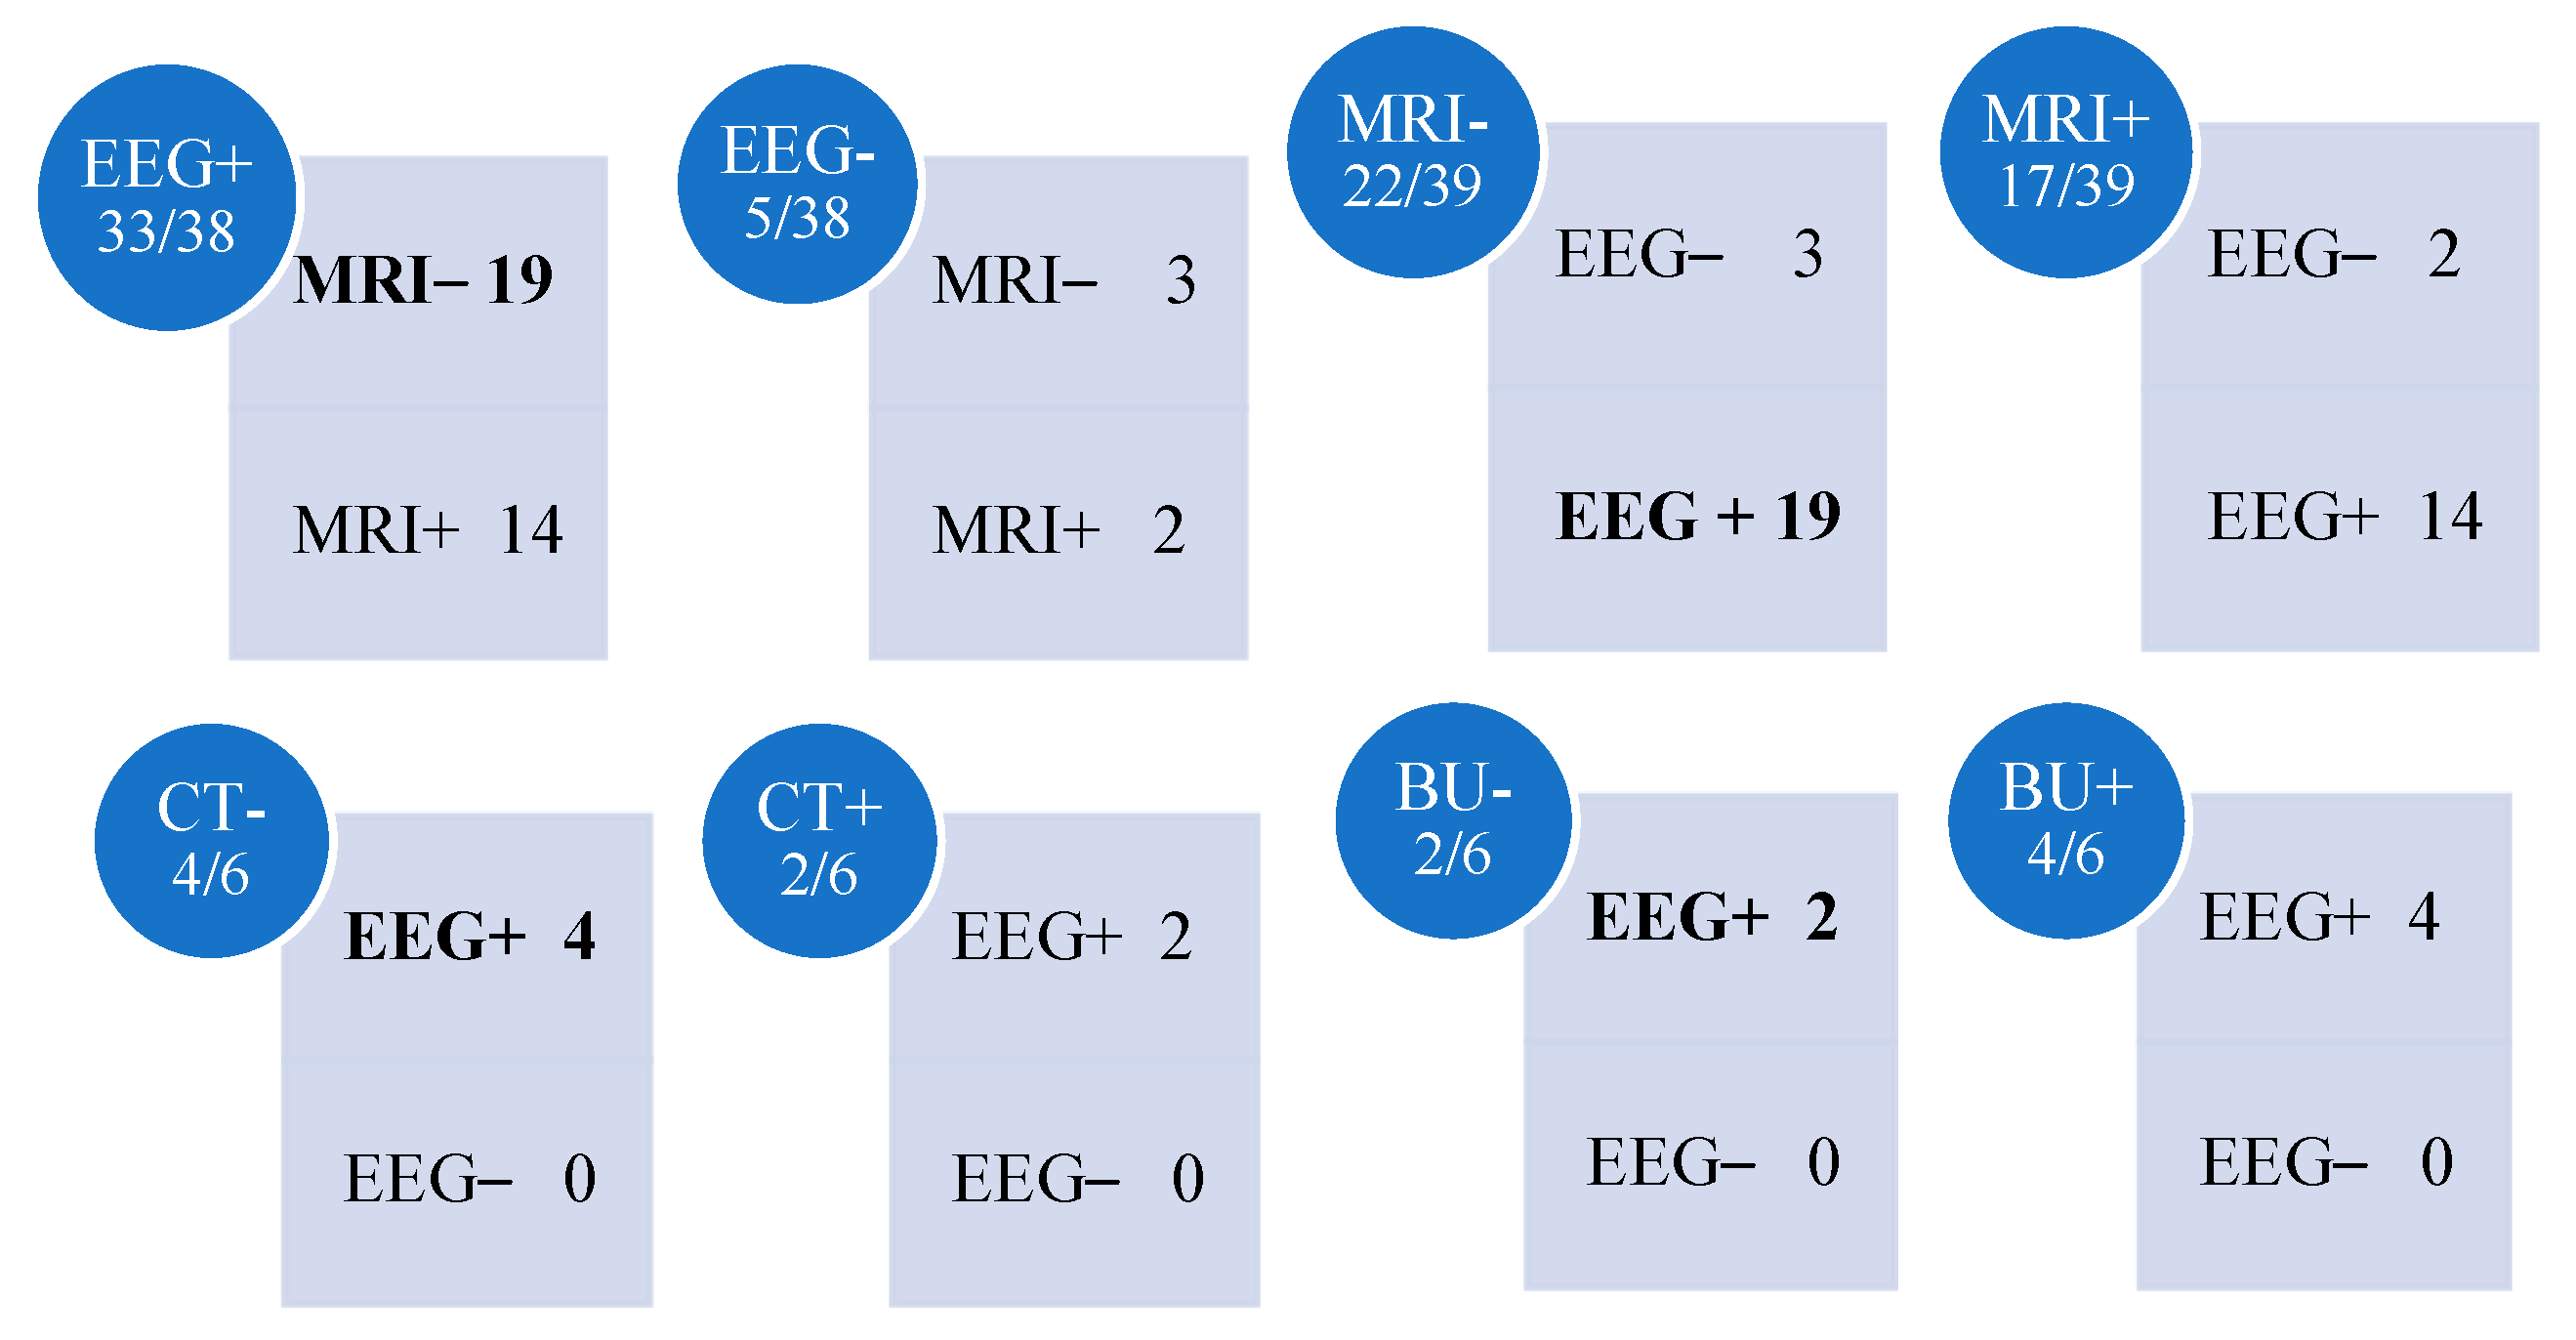

3.3. Electroencephalography

3.4. Neuroimaging